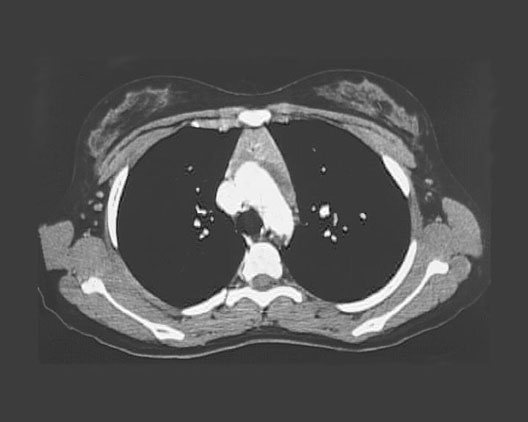

Chest CT of the Great Vessels

1. Superior vena cava

2. Sternum

3. Ascending aorta

4. Descending aorta

5. Left lung

6. Right lung

7. Scapula

8. Trachea